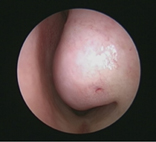

肥大之下鼻甲(左)

* 定義:鼻息肉是一種鼻腔內的軟組織增生,通常是由鼻黏膜所衍生出的非癌性腫大組織。它們通常以半透明狀或淡黃色的囊狀組織呈現。

* 症狀:鼻息肉最明顯的症狀就是鼻塞,且會有鼻涕倒流、黃鼻涕、嗅覺異常以及頭部悶痛等鼻竇炎相關症狀。甚至有時候病人忍受過久,可見鼻息肉從鼻孔突出或往鼻咽生長,有類似著鼻腔腫瘤完全堵塞的情形。